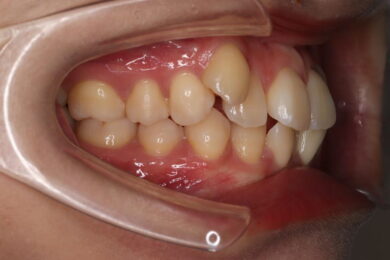

八重歯・叢生 マウスピース矯正(インビザライン)26歳女性 非抜歯

「前歯のガタガタ(叢生)と八重歯を治したい」を主訴に来院された患者様です。上下の歯にIPRを加え、歯列弓の拡大を行い、非抜歯で前歯のガタガタを整えました。顎間ゴムを用い、咬み合わせも改善されています。アライナーの装着時間が長く、チューイをしっかり使用していただけたため、非常に短時間で仕上がりました。

• 治療前